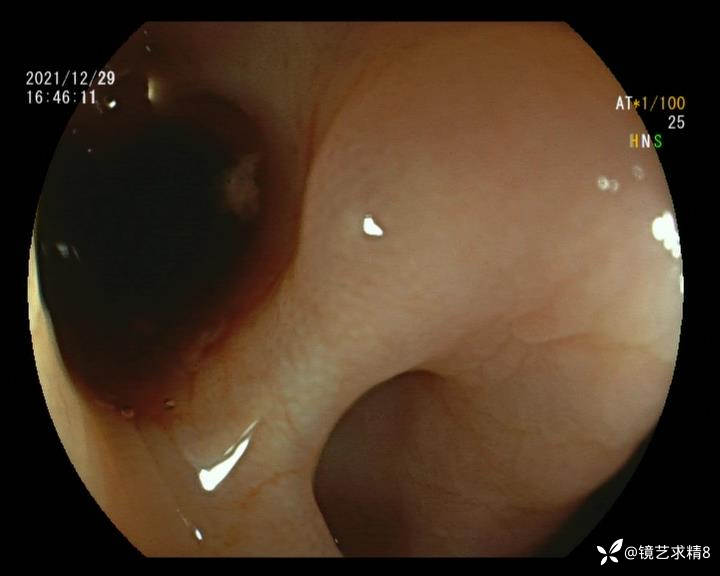

患者以消化道出血入院,胃镜未见异常,肠镜进入乙状结肠就看到很多憩室,同时还看到肠腔用清肠药后移动下来1枚尖锐的枣核,这么多憩室,这个枣核扎入憩室的机会非常大,推测应该是掉入一坑🕳就算出来还会有很多坑🕳🕳🕳等着,掉入憩室内很容易刺破血管,这可能就是消化道出血的原因,继续前进可以看到有一些憩室内翻,还有一些息肉,问题来了,那么多憩室,犯罪分子是抓住了,它在那些憩室内作过案?到达回盲部后挨个冲洗,但憩室大小又不足以把镜头进入憩室内观察,针对有血块的憩室冲洗后可疑出血的以夹子闭合或套扎,取出枣核,如果有锥形透明帽可能钻入憩室精准电凝效果更好,若内镜下操作失败介入治疗成功率更高,经内镜下治疗后观察未再出血出院。